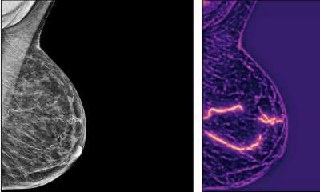

🩺 ИИ научился ΠΏΡ€ΠΎΠ³Π½ΠΎΠ·ΠΈΡ€ΠΎΠ²Π°Ρ‚ΡŒ риск сСрдСчно-сосудистых Π·Π°Π±ΠΎΠ»Π΅Π²Π°Π½ΠΈΠΉ Ρƒ ΠΆΠ΅Π½Ρ‰ΠΈΠ½ ΠΏΠΎ ΠΌΠ°ΠΌΠΌΠΎΠ³Ρ€Π°Ρ„ΠΈΠΈ

Анализируя ΠΊΠ°Π»ΡŒΡ†ΠΈΡ„ΠΈΠΊΠ°Ρ†ΠΈΡŽ Π°Ρ€Ρ‚Π΅Ρ€ΠΈΠΉ ΠΌΠΎΠ»ΠΎΡ‡Π½ΠΎΠΉ ΠΆΠ΅Π»Π΅Π·Ρ‹, Π°Π»Π³ΠΎΡ€ΠΈΡ‚ΠΌ ΠΎΡ†Π΅Π½ΠΈΠ²Π°Π» Π²Π΅Ρ€ΠΎΡΡ‚Π½ΠΎΡΡ‚ΡŒ ΠΈΠ½Ρ„Π°Ρ€ΠΊΡ‚Π°, ΠΈΠ½ΡΡƒΠ»ΡŒΡ‚Π° ΠΈ сСрдСчной смСрти. Π”Π°ΠΆΠ΅ лёгкая ΠΊΠ°Π»ΡŒΡ†ΠΈΡ„ΠΈΠΊΠ°Ρ†ΠΈΡ ΠΏΠΎΠ²Ρ‹ΡˆΠ°Π»Π° риск Π½Π° 30%, умСрСнная β€” Π±ΠΎΠ»Π΅Π΅ Ρ‡Π΅ΠΌ Π½Π° 70%, Π° выраТСнная β€” Π² 2–3 Ρ€Π°Π·Π°.

ИсслСдованиС, ΠΏΡ€ΠΎΠ²Π΅Π΄Ρ‘Π½Π½ΠΎΠ΅ ΡƒΡ‡Ρ‘Π½Ρ‹ΠΌΠΈ УнивСрситСта Π­ΠΌΠΎΡ€ΠΈ Π² БША, ΠΎΡ…Π²Π°Ρ‚ΠΈΠ»ΠΎ 123β€―762 ΠΆΠ΅Π½Ρ‰ΠΈΠ½ Π±Π΅Π· Ρ€Π°Π½Π΅Π΅ выявлСнных сСрдСчно-сосудистых Π·Π°Π±ΠΎΠ»Π΅Π²Π°Π½ΠΈΠΉ. Π Π΅Π·ΡƒΠ»ΡŒΡ‚Π°Ρ‚Ρ‹ ΠΏΠΎΠΊΠ°Π·Π°Π»ΠΈ, Ρ‡Ρ‚ΠΎ искусствСнный ΠΈΠ½Ρ‚Π΅Π»Π»Π΅ΠΊΡ‚ ΠΌΠΎΠΆΠ΅Ρ‚ ΠΏΠΎΠΌΠΎΡ‡ΡŒ Π²Ρ‹ΡΠ²Π»ΡΡ‚ΡŒ ΠΆΠ΅Π½Ρ‰ΠΈΠ½ ΠΈΠ· Π³Ρ€ΡƒΠΏΠΏΡ‹ высокого риска Π±Π΅Π· Π΄ΠΎΠΏΠΎΠ»Π½ΠΈΡ‚Π΅Π»ΡŒΠ½Ρ‹Ρ… обслСдований.